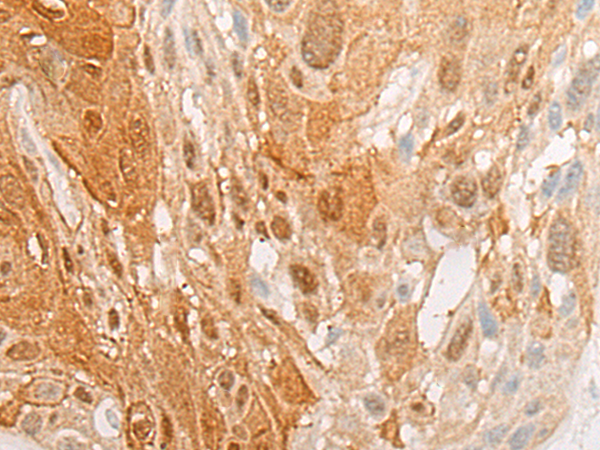

分类: 科研抗体货号: P06327别名: PL; HOX1; HOX1H; HOX1.8应用: WB,IHC反应种属: Human, Mouse